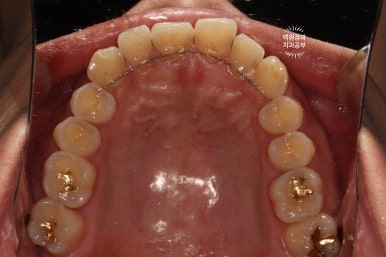

노란색 원으로 표시해둔 곳은 앞니 옆면 (인접면) 충치이고, 빨간색 원으로 표시해둔 곳은 기존 레진충전의 변색입니다.

교합면에서 보면, 충치가 뒤에서 봤을 때도 까맣게 보이는구나~ 라고 아실 수 있을겁니다.

사실 이번 30대 남자 환자분 같은 경우는 워낙 앞에서 충치가 잘 보이는 상황이라, 많은 설명이 필요하진 않았어요.